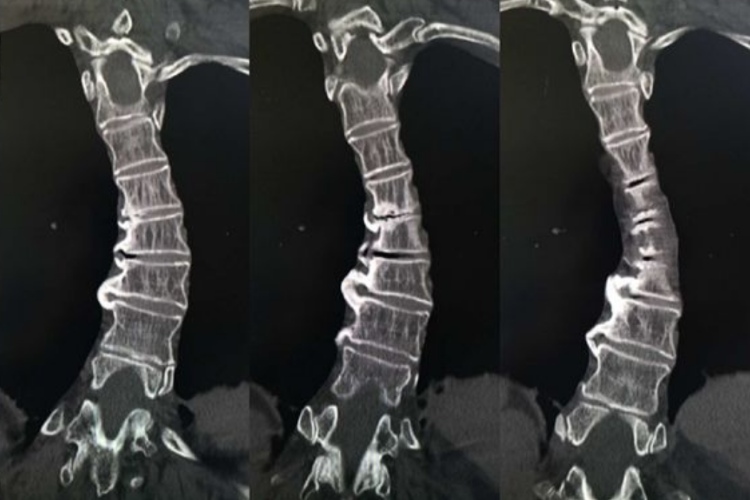

脊柱右侧弯属于脊柱的侧向弯曲畸形,进行CT检查可观察脊椎、肋骨、椎弓根、横突的形态,可以显示有无骨性畸形,有助于全面了解脊柱发育异常及矢状面畸形。患者检查可见部分脊柱节段凸向右侧,还可有多个弯曲,脊柱偏离中线。较严重时可能会导致两肩高低不平,前弯时背部两侧不对称,影响心肺功能。